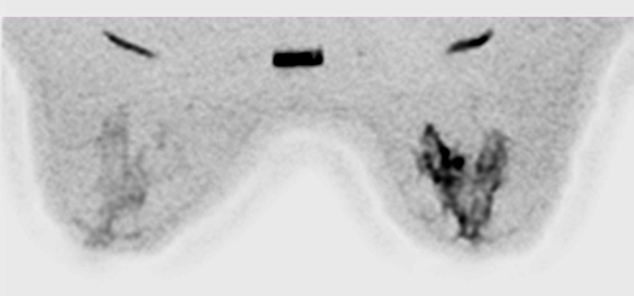

Con nuestra Nueva RM Digital podemos obtener resultados increibles incluso en pacientes inquietos, presencia de artefactos de movimiento y Contraste de agua, grasa, en fase y fuera de fase en una sola adquisición para obtener imágenes libres de grasa.

Con adquisición de imágenes en T1W como VIBRANT/VIBRANT Flex, enhanced DWI, espectroscopia con BREASE MR, bobinas dedicadas de 16 canales de recepción y herramientas avanzadas de post-procesado para recabar toda la información que necesita para diagnosticar con total seguridad y lograr resultados positivos para sus pacientes.

Con la nueva RM digital podemos obtener imágenes de cada mama con saturación de grasa y además adquirir imágenes bilaterales en plano axial o sagital, lo que nos ha permitido mejorar de forma notable nuestro programa de diagnóstico por imagen del cáncer de mama.”